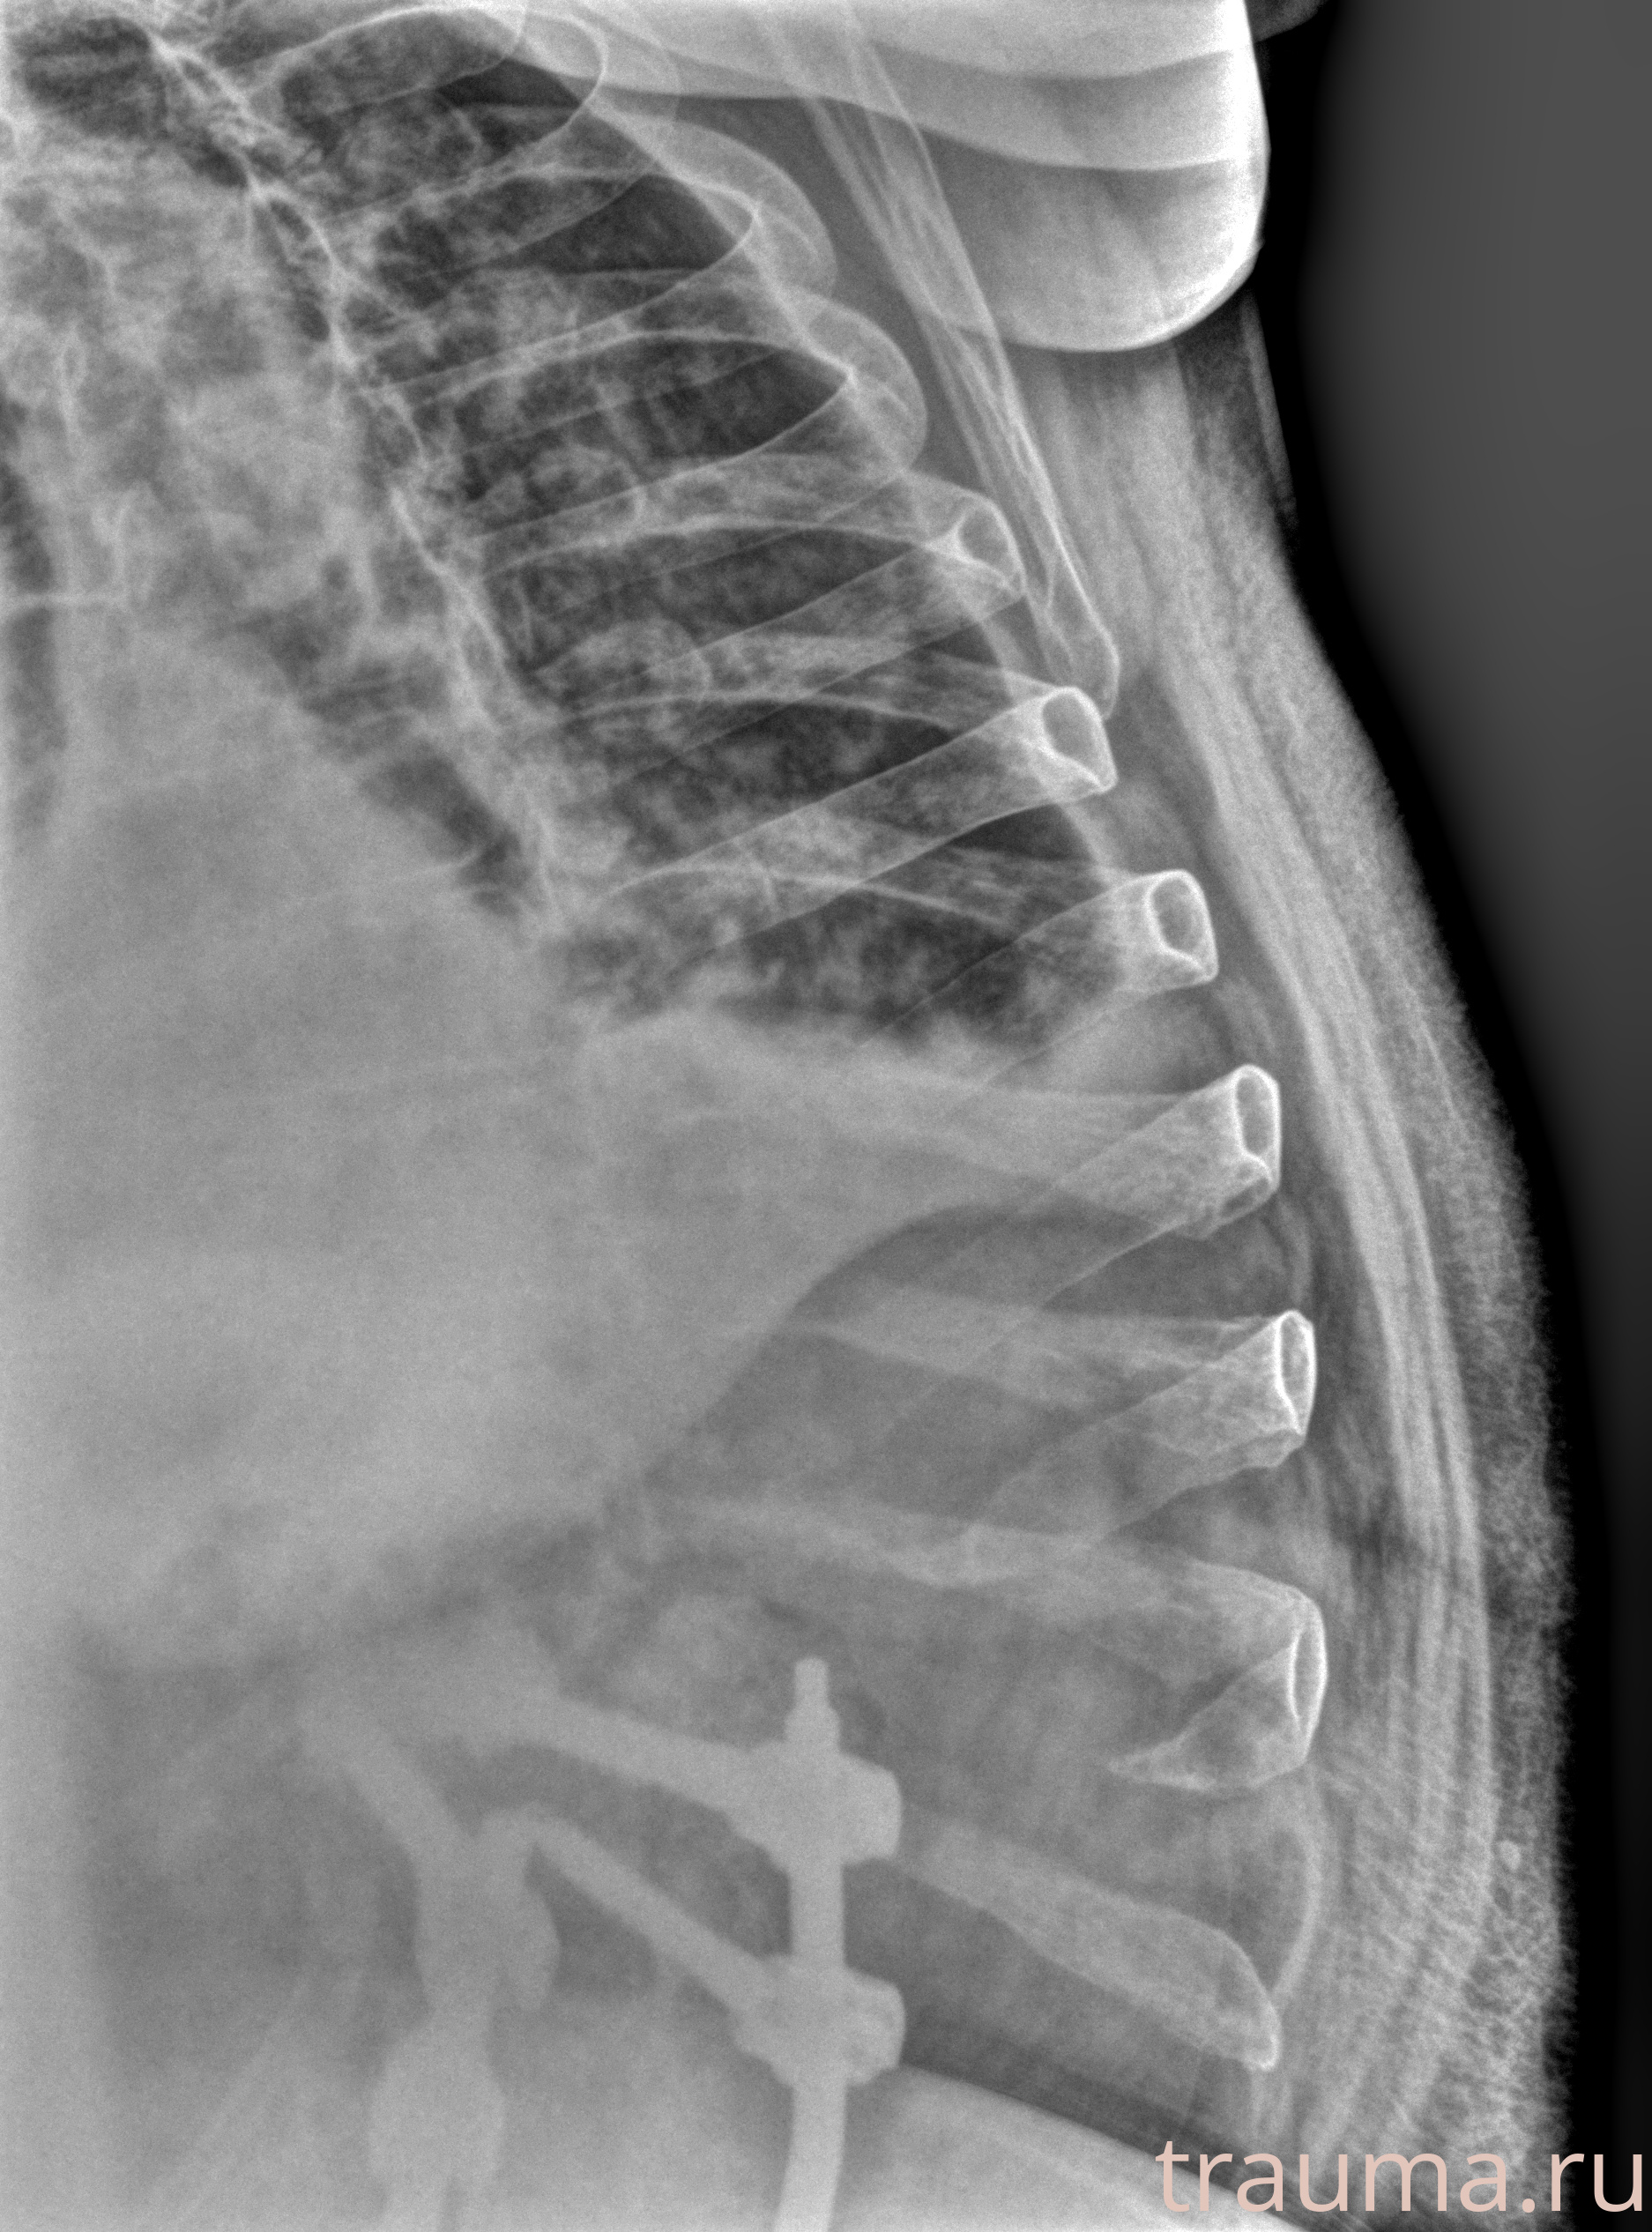

Рентген на дому: по вашему адресу приезжает врач-рентгенолог, травматолог-ортопед с мобильным рентгеновским аппаратом, проводит диагностику травмы или заболевания, делает необходимые рентгенограммы, дает рекомендации по дальнейшему лечению. Получить качественные снимки в домашних условиях возможно благодаря уникальной методике, разработанной МосРентген Центром для института  Склифосовского